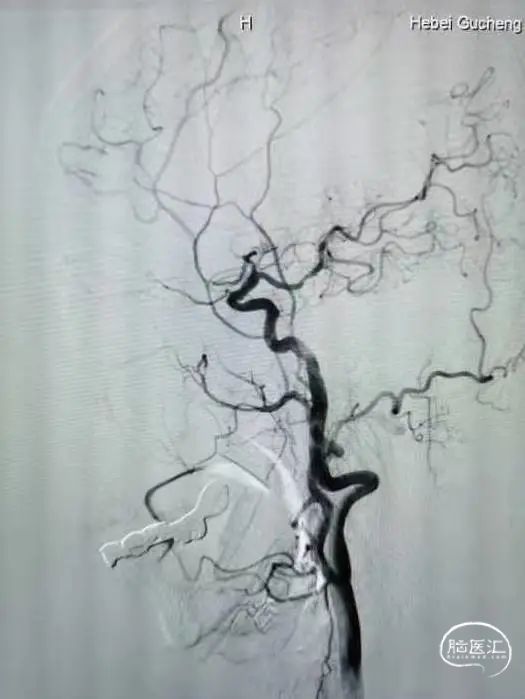

术前DSA的正位、侧位造影:

右侧颈内动脉DSA: